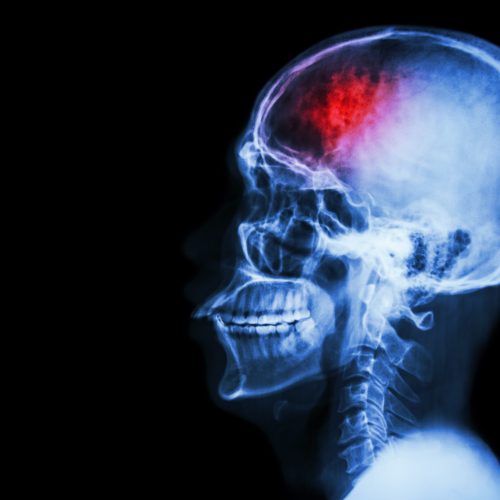

מה זה שבץ או אירוע מוחי? שבץ מוחי (שנקרא גם "אירוע מוחי") הוא אירוע פתאומי שגורם נזק למוח. ישנם 2 סוגים של שבץ מוחי: איסכמיה מוחית– זהו מצב שבו קריש דם חוסם את אחד העורקים שמובילים את הדם למוח. כתוצאה מכך, כלי הדם נסגר ובגלל חוסר זרימת הדם למוח מתפתחת פגיעה עצבית. דימום ספונטני מוחי...